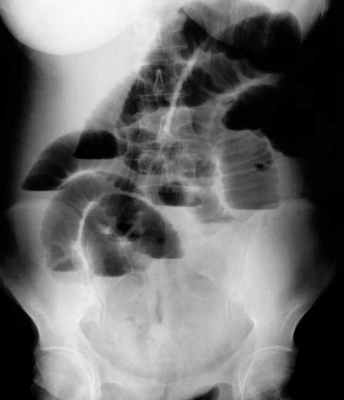

Рентгенологическое исследование является основным специальным методом диагностики ОКН. При этом выявляются следующие признаки:

- Чаша Клойбера – горизонтальный уровень жидкости с куполообразным просветлением над ним, что имеет вид перевернутой вверх дном чаши. При странгуляционной непроходимости могут проявляться уже через 1 час, а при обтурационной непроходимости — через 3-5 часов с момента заболевания. Количество чаш бывает различным, иногда они могут наслаиваться одна на другую в виде ступенчатой лестницы.

- Кишечные аркады. Получаются, когда тонкая кишка оказывается раздутой газами, при этом в нижних коленах аркад видны горизонтальные уровни жидкости.

- Симптом перистости (поперечная исчерченность в форме растянутой пружины) встречается при высокой кишечной непроходимости и связан с растяжением тощей кишки, имеющей высокие циркулярные складки слизистой. Контрастное исследование желудочно-кишечного тракта применяется при затруднениях в диагностике кишечной непроходимости. Больному дают выпить 50 мл бариевой взвеси и проводят динамическое исследование пассажа бария. Задержка его до 4-6 часов и более дает основание заподозрить нарушение двигательной функции кишечника.

Рентгенологическая диагностика острой кишечной непроходимости. Уже через 6 ч от начала заболевания имеются рентгенологические признаки кишечной непроходимости.

1. Рентгенологическое обследование является основным специальным методом диагностики ОКН. Обзорная рентгенография брюшной полости должна проводиться при малейшем подозрении на ОКН. При этом выявляется ряд признаков. В норме газ имеется в ободочной кишке. Появление газа в тонкой кишке указывает на непроходимость. Характер скопления газа в просвете кишечника различается при разных вариантах КН (рис. 1). Рисунок 1. Схема скопления газа в просвете кишечника при разных вариантах КН. а - высокая тонкокишечная непроходимость. Возможно наличие единичных горизонтальных уровней жидкости и газа. Наличие газа в толстой кишке не характерно Рисунок 1. Схема скопления газа в просвете кишечника при разных вариантах КН. б - низкая тонкокишечная непроходимость. Обычно видны множественные горизонтальные уровни жидкости и газа (чаши Клойберга). Наличие газа в толстой кишке не характерно Рисунок 1. Схема скопления газа в просвете кишечника при разных вариантах КН. в - странгуляционная кишечная непроходимость. Могут быть как единичные, так и множественные горизонтальные уровни жидкости и газа. Наличие газа в толстой кишке не характерно. Обычно по снимкам удается определить, петли какой кишки - тонкой, толстой или обеих - растянуты газом. При наличии газа в тонкой кишке хорошо видны спиралевидные складки слизистой оболочки (Керкринговы складки), занимающие весь поперечник кишки.

На рентгенограммах, полученных в положении стоя или лежа на боку, обычно видны горизонтальные уровни жидкости и газа (рис. 2). Рисунок 2. Обзорная рентгенограмма брюшной полости. Видны чаши Клойбера, уровни жидкости. Заполненные газом кишечные петли имеют вид опрокинутых чаш (чаши Клойбера). Они появляются при странгуляции через 1-2 ч после начала заболевания, при обтурации - через 3-5 ч. По размерам чаш Клойбера, их форме и локализации можно судить об уровне непроходимости.

При тонкокишечной непроходимости чаши Клойбера небольших размеров, ширина горизонтального уровня жидкости больше, чем высота столба газа над ним. Обычно наблюдается большое количество горизонтальных уровней с изменением их расположения в течение времени и перемещением жидкости из одной петли в другую. Горизонтальные уровни жидкости ровные. На фоне газа хорошо видны складки слизистой оболочки (складки Керкринга), принимающие форму растянутой спирали.

При непроходимости тощей кишки горизонтальные уровни жидкости локализуются в левом подреберье и эпигастральной области. При непроходимости в терминальном отделе подвздошной кишки уровни жидкости расположены в области мезогастрия.

При тонкокишечной непроходимости, кроме чаш Клойбера, на рентгенограммах видны растянутые газом кишечные петли, принимающие форму «аркад» или «органных труб», похожих на перевернутые буквы J и U.

При толстокишечной непроходимости горизонтальные уровни жидкости расположены по периферии брюшной полости, в боковых отделах живота, и их меньше, чем при тонкокишечной непроходимости. Высота чаш Клойбера преобладает над шириной. На фоне газа видны полулунные складки слизистой оболочки («гаустры»). Уровни жидкости не имеют ровной поверхности («зеркала»), что обусловлено наличием в толстой кишке плотных кусочков кала, плавающих на поверхности жидкого кишечного содержимого.

B ранней стадии непроходимости на обзорных рентгенограммах в положении лёжа будут видны умеренно pаздутые петли тонкой кишки с небольшим содержанием воздуха. При съёмке в положении стоя или на левом боку определяются множественныe уровни газ-жидкость. Складки Керкринга на ранних стадиях видны, по мере прогрессирования обструкции петли растягиваются и складки смазываются. Иногда очень сложно отличить раздутые петли тонкой кишки от толстой.

Обзорная рентгенография живота в положении лёжа